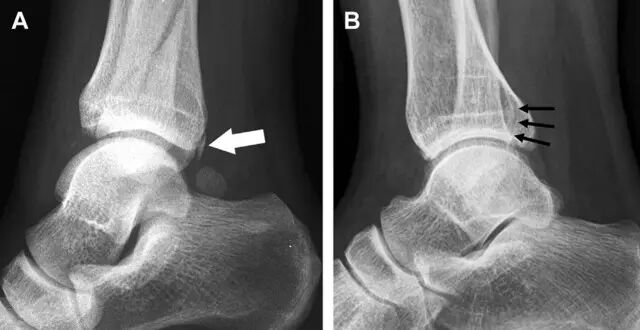

急诊科医生常遇到的一个问题是:踝关节疼痛。对于这类患者,想要分辨是否存在骨折,X 线检查是主要手段。然而,由于各种原因,有些踝部骨折非常容易漏诊。

首先,来看踝关节骨折的高危区(图 1)。

图 1 踝部探查模板。阅片时,需对踝关节的前后位片(A)、内旋转位片(B)侧位片(C)仔细阅读,逐一详细排查。上图中的骨折:1. 内踝骨折,2. 外踝骨折,3. 胫骨结节骨折,4. 胫骨后踝骨折,5. 距骨骨软骨骨折,6. 距骨外侧突骨折,7. 距骨后突骨折,8. 距骨舟骨关节背侧骨折,9. 跟骨前突骨折,10. 跟骨骨折嵌插入趾短伸肌,11. 第五跖骨底骨折

涉及到三角韧带和外侧副韧带(LCL)的复杂性骨折常常不难发现,尤其是存在表面软组织肿胀时。然而,后胫腓韧带牵拉引起的胫骨后踝骨折则很难发现。这些骨折大小不一(图 2),却很重要,因为他们常与胫骨远端螺旋骨折有关,或者是三踝骨折的一部分。

图 2 胫骨后踝骨折。A 侧位片示来源于胫骨后踝的一个小骨折碎片(箭头),因踝部扭伤导致;B 另一位跖屈损伤的患者,侧位片示一个大骨折块(箭头)

Tillaux 骨折,是足外旋外展时,胫腓前韧带牵拉引起的一种胫骨结节撕脱性骨折。斜位片上可见典型表现(图 3)。

图 3 摔倒后胫骨结节骨折。A 正位片示一细小斜型骨折线(箭头);B 侧位片示正常;C 冠状位 CT 三维成像更清晰地显示了骨折线和骨折块大小(空箭头);D 矢状位 CT 多维重建图像示骨折位置(箭头)

距骨外侧突骨折常因踝外翻背屈时,跟骨上外侧面撞击距骨外侧突下缘导致,或偶尔由踝内翻引起,被称为「滑雪板者骨折」。这种骨折只能在踝关节正位片上发现,而且外踝远端表面软组织肿胀往往是一个重要线索(图 4)。

图 4 距骨外侧突骨折。A 正位片示内翻损伤所致的距骨外侧突撕脱性骨折(箭头);B 另一位患者,踝外翻损伤导致典型的「滑雪板者骨折」,X 片上可见一较大的三角形骨折块(方框);C 第二位患者的 MRI 矢状位 T1 加权像示横行骨折(箭头)

距骨后突有内侧结节和外侧结节,距骨后突内侧结节撕脱性骨折常发生在背屈内旋的暴力作用下。严重跖屈时,胫骨后缘和跟骨挤压距骨后突外侧结节呈楔形,易发生粉碎性骨折。这些骨折细微且需与三角骨鉴别。侧位片观察距骨后突骨折最佳,常规拍片很难发现,当高度怀疑这种骨折又没法做 CT 时,建议加做多个角度的外旋斜位片(图 5)。

图 5 距骨后突骨折。侧位片(A)和 MRI 矢状位 T1 加权像(B)均示后外侧突的简单骨折(箭头),再次阅片时才发现 X 线片上的骨折;侧位片(C)和 CT 横断面图像示后内侧突的粉碎型骨折(箭头)

呈 Y 形的分歧韧带附着于跟骨前突上,是维持踝关节跖屈和背屈稳定性的重要结构。跟骨前突骨折常发生于足跖屈内旋、分歧韧带被牵拉时,或者足背屈外旋、骰骨和距骨挤压前突时。而这些骨折在初次 X 线检查时常常被漏诊掉。踝部侧位片诊断这些骨折最佳,准确诊断的关键点在于,必须仔细查看是否存在骨皮质中断(图 6)。如果侧位片可疑,建议加做斜位片协助诊断。

图 6 跟骨前突骨折。A 侧位片示跟骨前突骨折(箭头),与舟骨的重叠使骨折显示模糊;B 另一位患者的侧位片示内翻损伤所致的骨折(箭头),这种损伤机制引起小块的骨折

另一种重要的跟骨撕脱性骨折,于足内翻时发生在趾短伸肌的起点处。观察来自跟骨背外侧的、不同大小的骨折块,前后位 X 片最适合不过了(图 7)。

图 7 溜冰受伤的患者,趾短伸肌跟骨撕脱性骨折。正位片示 2 个骨折块(箭头)来源于跟骨前外侧、趾短伸肌的起点处。踝关节外侧远端是否存在软组织水肿是一个重点观察点

与跗跖关节韧带相关的骨折常由旋前或旋后的跖屈损伤引起。尽管跗跖关节骨折脱位仅占所有骨折的 0.2%,但是约 20% 的这些骨折在初次检查时被漏诊。初次 X 片可能示正常,但是负重位 X 线片常常提示脱位或半脱位。

典型表现:第二跖骨底和内侧楔骨之间的骨折碎片,跖骨间间隙增宽(图 8)。脱位亦可发生在舟骨-内侧楔骨关节,导致另一种变异的跗跖关节损伤(图 9A)。此外,骰骨的小块皮质撕脱在足部斜位片上可清晰显示(图 9B)。